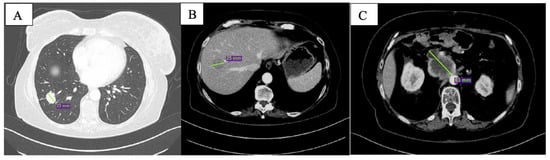

After the 6th month of therapy with olaparib, clinical conditions worsened with uncontrolled abdominal pain and G3 fatigue per CTCAE v. 5.0 [13]. At CT scan, multiple new liver lesions were observed (Figure 4A); the peripancreatic tissue was augmented with celiac trunk encasement (Figure 4B). Peritoneal carcinosis was also evident.

Figure 4.

CT scan after 6 months of olaparib: new liver lesions are documented (A) and peripancreatic tissue is increased (B).